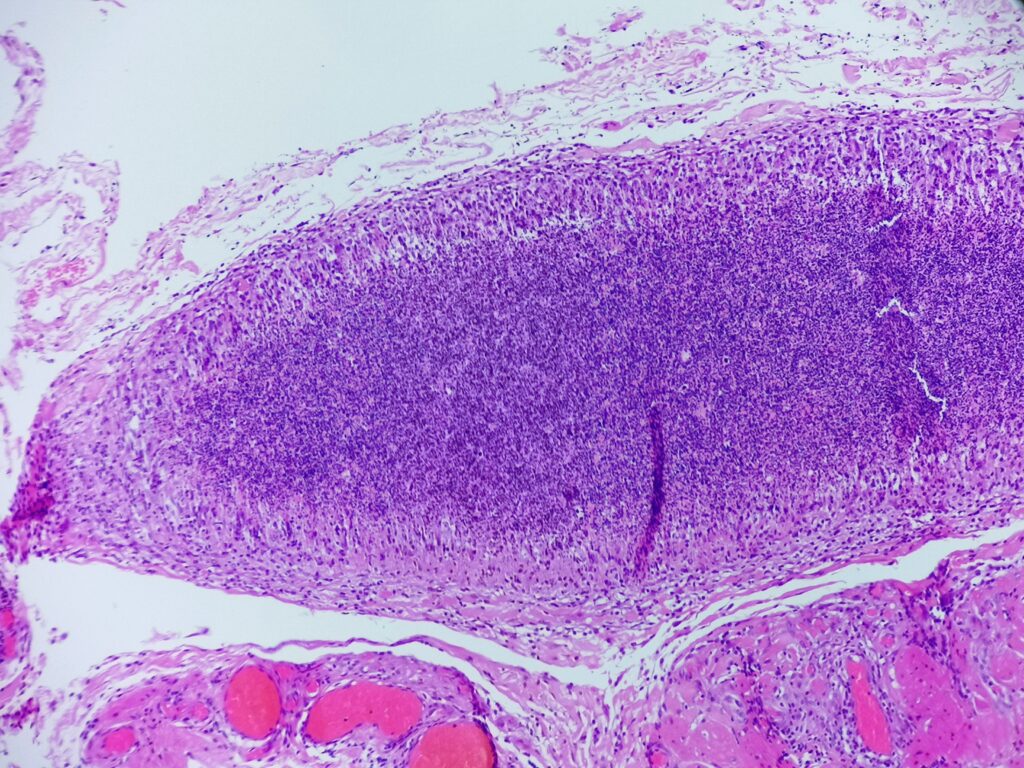

Obrazy mikroskopowe:

Cechy charakterystyczne:

- cienkościenna torbielowata struktura składająca się z tkanki łącznej (krzyżyk) wysłana jednowarstwowym nabłonkiem (czerwona strzałka) od kostkowego po walcowaty, z pojedynczymi komórkami rzęskowymi – torbiel nasienna patrz przypadek nr 105. SMP

- poza światłem zmiany obecne są plemniki (gwiazdka) z otaczającym odczynem z histiocytów (komórki o owalnym lub okrągłym jądrem komórkowym stosunkowo obfitej lekko kwasochłonnej cytoplazmie, niebieska strzałka), nieliczne limfocyty i komórki wielojądrowe (zielona strzałka) – ziarniniak

- brak komórek atypowych, martwicy centralnej, grzybów bądź innych mikroorganizmów

Ziarniniak nasienny (sperm granuloma)